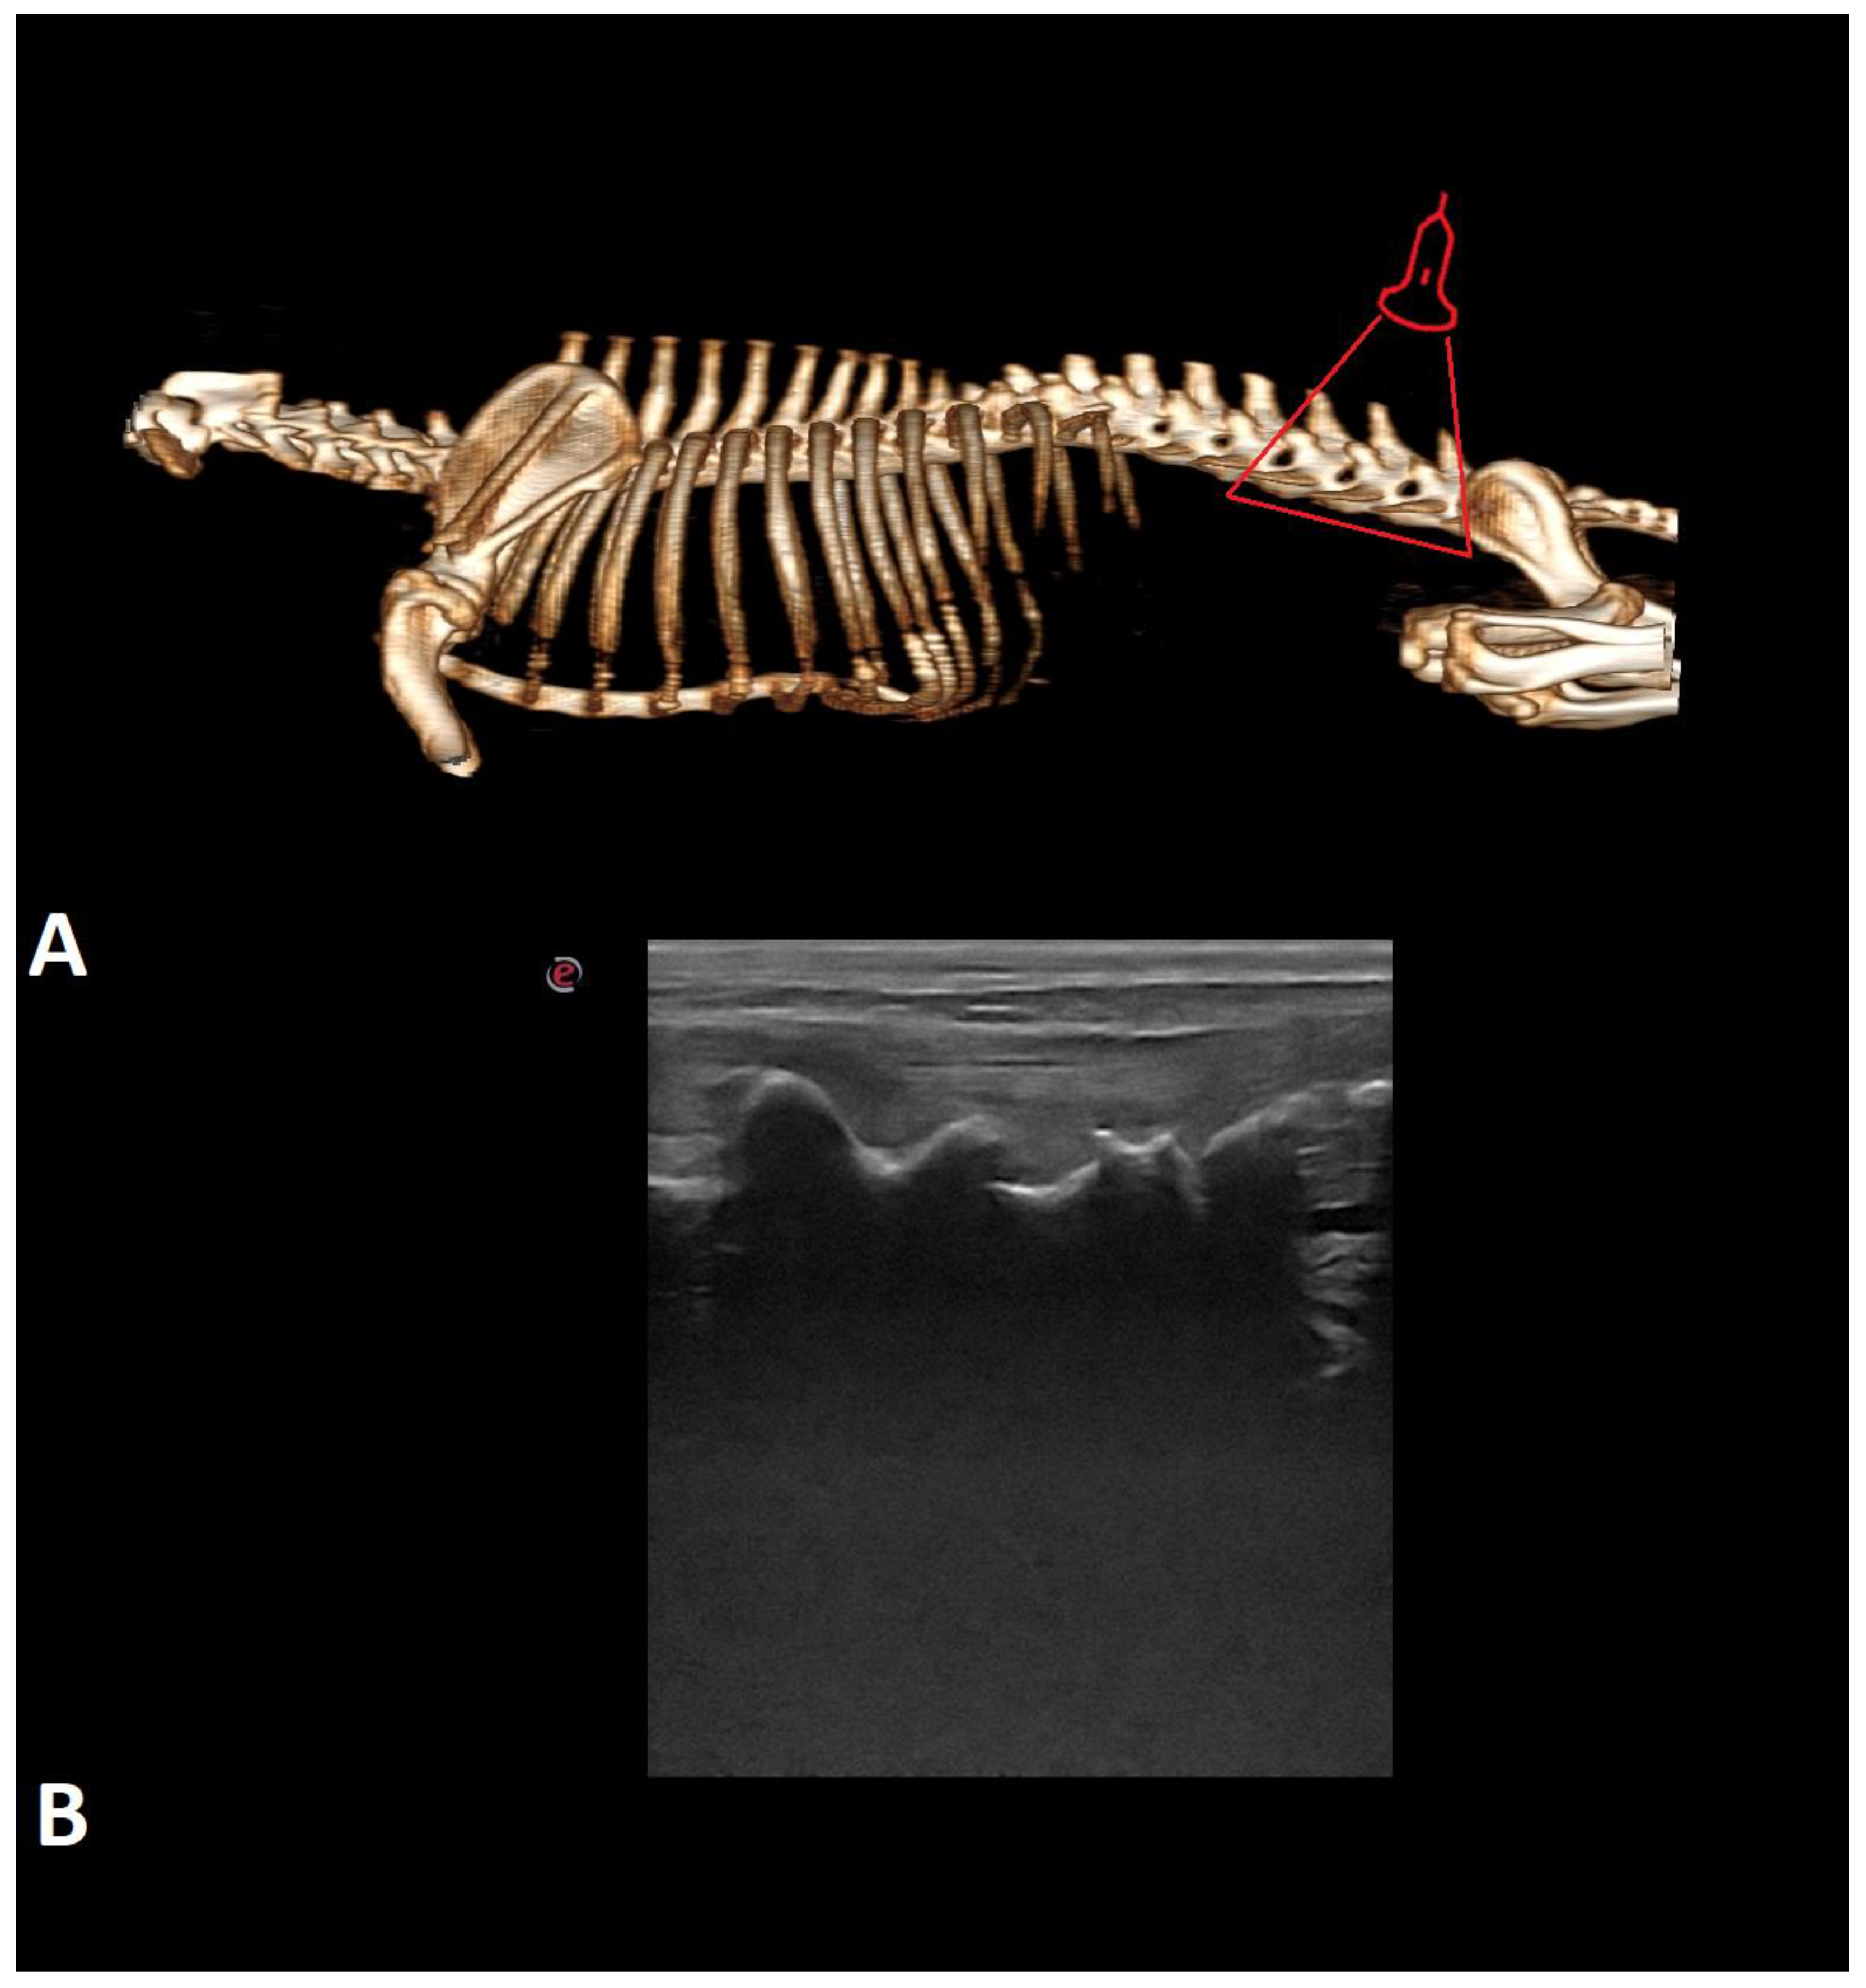

- Lopes, É.R.; Bellegard, G.M.; Cury, F.S.; Abreu, F.A.; Ambrósio, C.E.; Carregaro, A.B.; Hage, M.C.F. Evaluation of the applicability of musculoskeletal ultrasonography of the thoracolumbar and lumbar spine segment of healthy dogs. Pesqui. Veterinária Bras. 2018, 38, 2278–2283. [Google Scholar] [CrossRef]